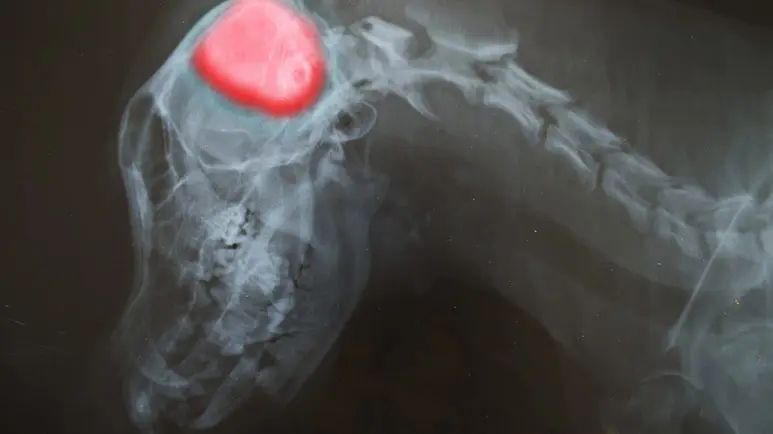

A spinal tap does carry some risk for certain animals. Your pet may require a magnetic resonance imaging (MRI) or computerized tomography (CT) scan of the brain prior to a spinal tap to look for signs of elevated intracranial pressure that can increase the risk for the procedure. Brain imaging can also be helpful in ruling out other causes of neurologic disease like a brain tumor.